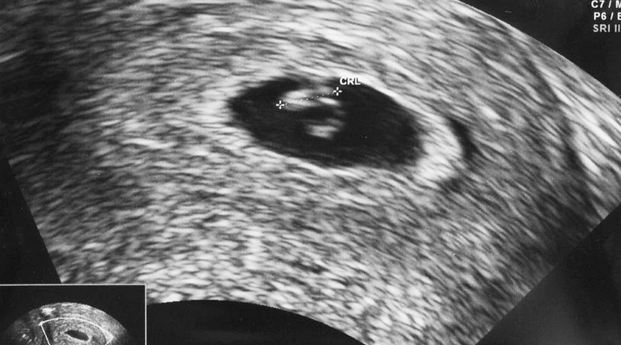

Pemeriksaan USG

Pemeriksaan USG merupakan cara lain untuk menghitung usia kehamilan dengan menghitung ukuran-ukuran tampilan visual bayi pada layar, tetapi hanya dapat dilakukan oleh dokter kandungan.

Untuk Ibu yang merasa siklus haid terakhirnya terjadi dalam 20 minggu terakhir, umumnya yang diukur adalah diameter rata-rata gestational sac (kantung kehamilan) dan jarak dari puncak kepala hingga ujung tubuhnya (disebut juga crown rump length).

Sedangkan apabila Ibu merasa mendapatkan haid terakhirnya sudah lebih dari 20 minggu yang lalu, maka yang diukur oleh USG adalah diameter tulang kepala (disebut juga biparietal diameter), lingkar kepala, lingkar perut, dan panjang paha.

Seluruh hasil pengukuran tersebut akan dikombinasikan, dan hasil akhirnya menunjukkan estimasi usia kehamilan Ibu. Umumnya cara ini lebih akurat dalam mendefinisikan usia kehamilan daripada metode siklus menstruasi, namun hasil penghitungannya dapat pula sedikit variatif daripada usia aslinya.